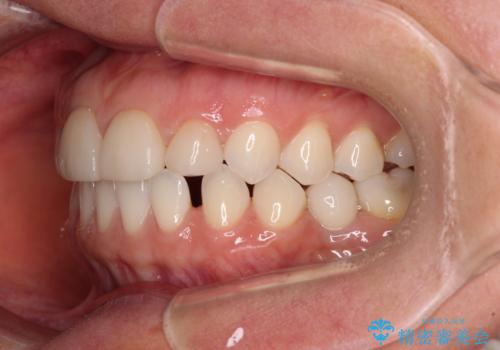

- 大きすぎる上顎前歯と、隙間の空いた下顎歯列を気にして来院された患者様です。

上顎前歯にはセラミッククラウンが装着されており、顔や他の歯と比較して幅の大きい状態でした。

下顎前歯は空隙歯列弓であったので、アンカースクリューとワイヤー装置を用いてスペースを閉じていくこととし、上顎前歯は矯正治療用の仮歯に置き換えた上で、仮歯の大きさを削って小さくしながら、上下前歯部の部分矯正を行うこととしました。